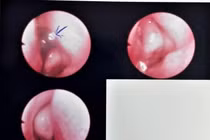

| Hàm răng giả được bác sĩ lấy ra từ thực quản bệnh nhân. Ảnh BVCC |

Bệnh nhân sau đó được chuyển vào Khoa Gây mê - Hồi sức. Với sự phối hợp nhịp nhàng của đội ngũ y bác sĩ, ca phẫu thuật nội soi ống cứng đã diễn ra thành công, lấy ra dị vật là cung răng giả sắc nhọn.

Ca nội soi kéo dài khoảng 40 phút, dị vật được lấy ra có kích thước 3x5cm. Do cấu tạo của hàm răng giả có nhiều mấu, bám chặt vào thực quản, gây khó khăn hơn so với các dị vật thông thường khác.